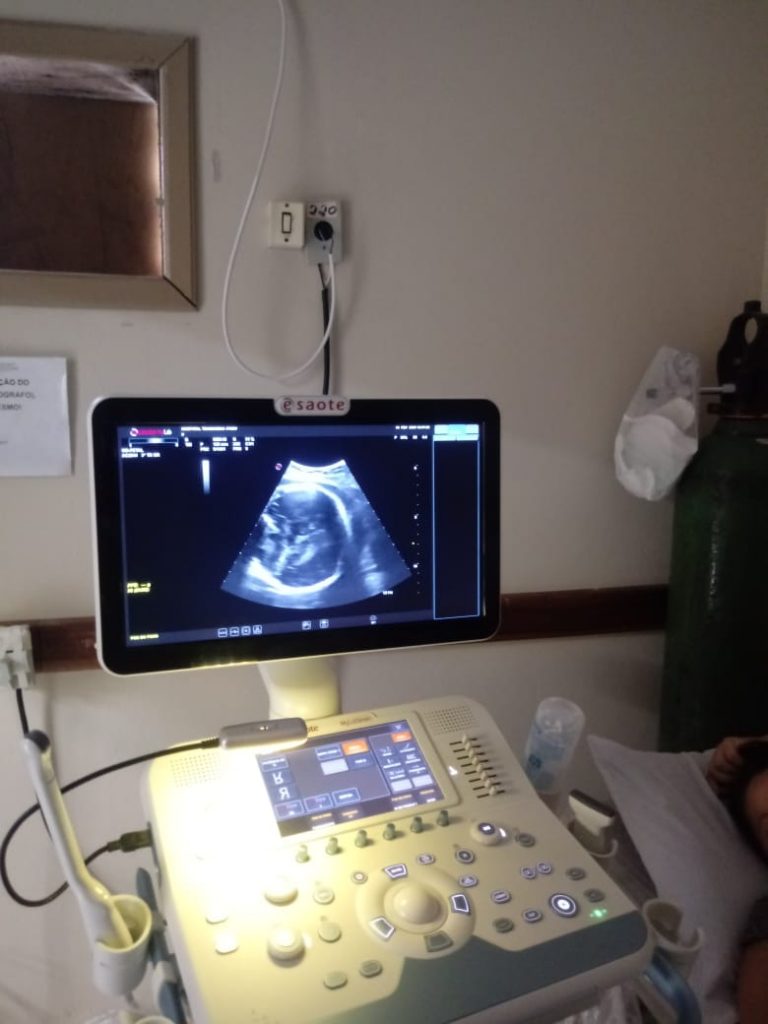

No domingo (16), Shayenne Pereira chegou ao Centro Obstétrico do Hospital Tramandaí com 39 semanas de gestação, prestes a realizar uma cesariana, já que, conforme exame anterior, o bebê estava com “apresentação transversa”. Ao realizar a ecografia, entretanto, a Dra. Izabelle constatou que havia “apresentação pélvica”. Essas apresentações dizem respeito ao posicionamento do bebê no ventre da mãe. Imediatamente, a doutora conversou com Shayenne, explicando a possibilidade de realizar uma manobra para reposicionar a criança, virando-a através de movimentos manuais no abdômen materno.